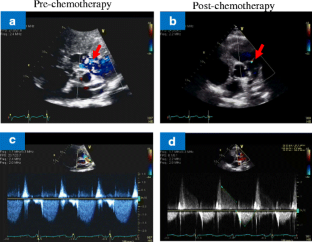

Fig. 2